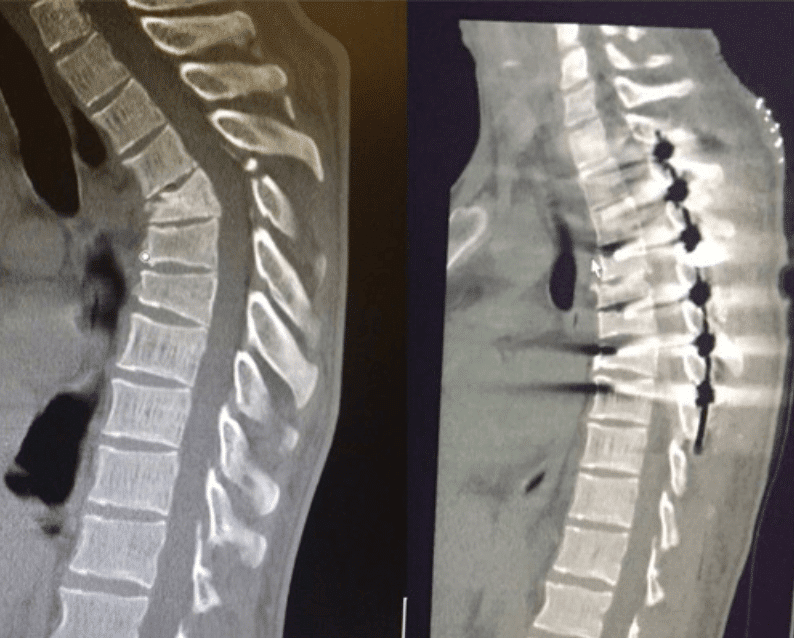

Luckily, the operation went great! Dr. Melamed and his staff did an amazing job fusing my T2-T8 and correcting the 40 degree kyphosis in my thoracic section of my spine. After a week in the hospital, my wife Georgia and I have spent the last 3 weeks resting at home.

Wednesday morning (04/12/17) Jimmy went into surgery with Dr Melamed in CA. The surgery lasted over 6 hours and 7 vertebrae were fused. The damage to the vertebrae was extreme and the surgeon did an amazing job re-breaking/aligning and fixing the spine. Everything went well, however getting the pain under control is the main focus as of the moment.

After talking with Dr. Melamed with Disc MD Group in L.A, He had also agreed to the fusion but seemed genuinely concerned about my condition. He explained to me that I have a 30 degree kyphosis “A hunch back basically” in the Thoracic part of my spine. He went on to explain that by having the rods and fusion done of my back without the spinal Alignment done will have a terrible effect me in my quest to get back to living pain free. Not many surgeons are willing to do this surgery because it does involve breaking the spine even more to correct it. That being said, the possibility of being in better spine health than even before the injury excites me.